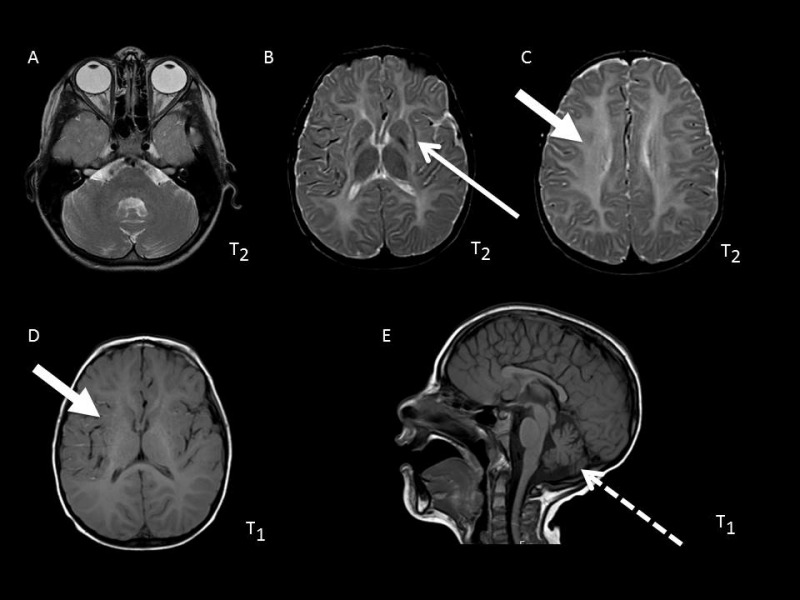

• 伴基底节、小脑萎缩的髓鞘形成低下(H-ABC) [van der Knaap et al 2002Sasaki et al 2009Blumkin et al 2014、Ferreira et al 2014Hamilton et al 2014Sagnelli et al 2016Tonduti et al 2016]的特点为(图 1):

• 基底节进行性萎缩,以新纹状体(即壳核和尾状核)为主,常伴随着壳核体积的明显减小(随病情进展可消失),尾状核头部受累程度较轻。丘脑和苍白球通常不会受累。 需注意的是,尽管许多H-ABC患者到2岁时壳核的变化已很明显,但在一些儿童中这种变化可能直到儿童晚期才出现。

• 大脑白质区域,包括幕上白质、胼胝体和内囊在内,出现弥漫性髓鞘形成低下,表现为T2加权像轻度高信号、T1加权像典型的等信号或轻度高信号

• 与灰质结构相比,小脑白质T1加权像呈等信号或轻度高信号或低信号。蚓部受累为主的小脑萎缩是H-ABC常见的、但并非必不可少的临床特征。

• TUBB4A相关的孤立髓鞘形成低下的特点是小脑可受累或不受累,并且新纹状体受累不明显[Pizzino et al 2014Purnell et al 2014]。

Figure 1.

图 1.  MRI表现A. 与灰质结构相比,小脑白质T1加权像呈等信号或轻度高信号或低信号;小脑萎缩蚓部受累明显。 脑干信号无特殊改变(更多...